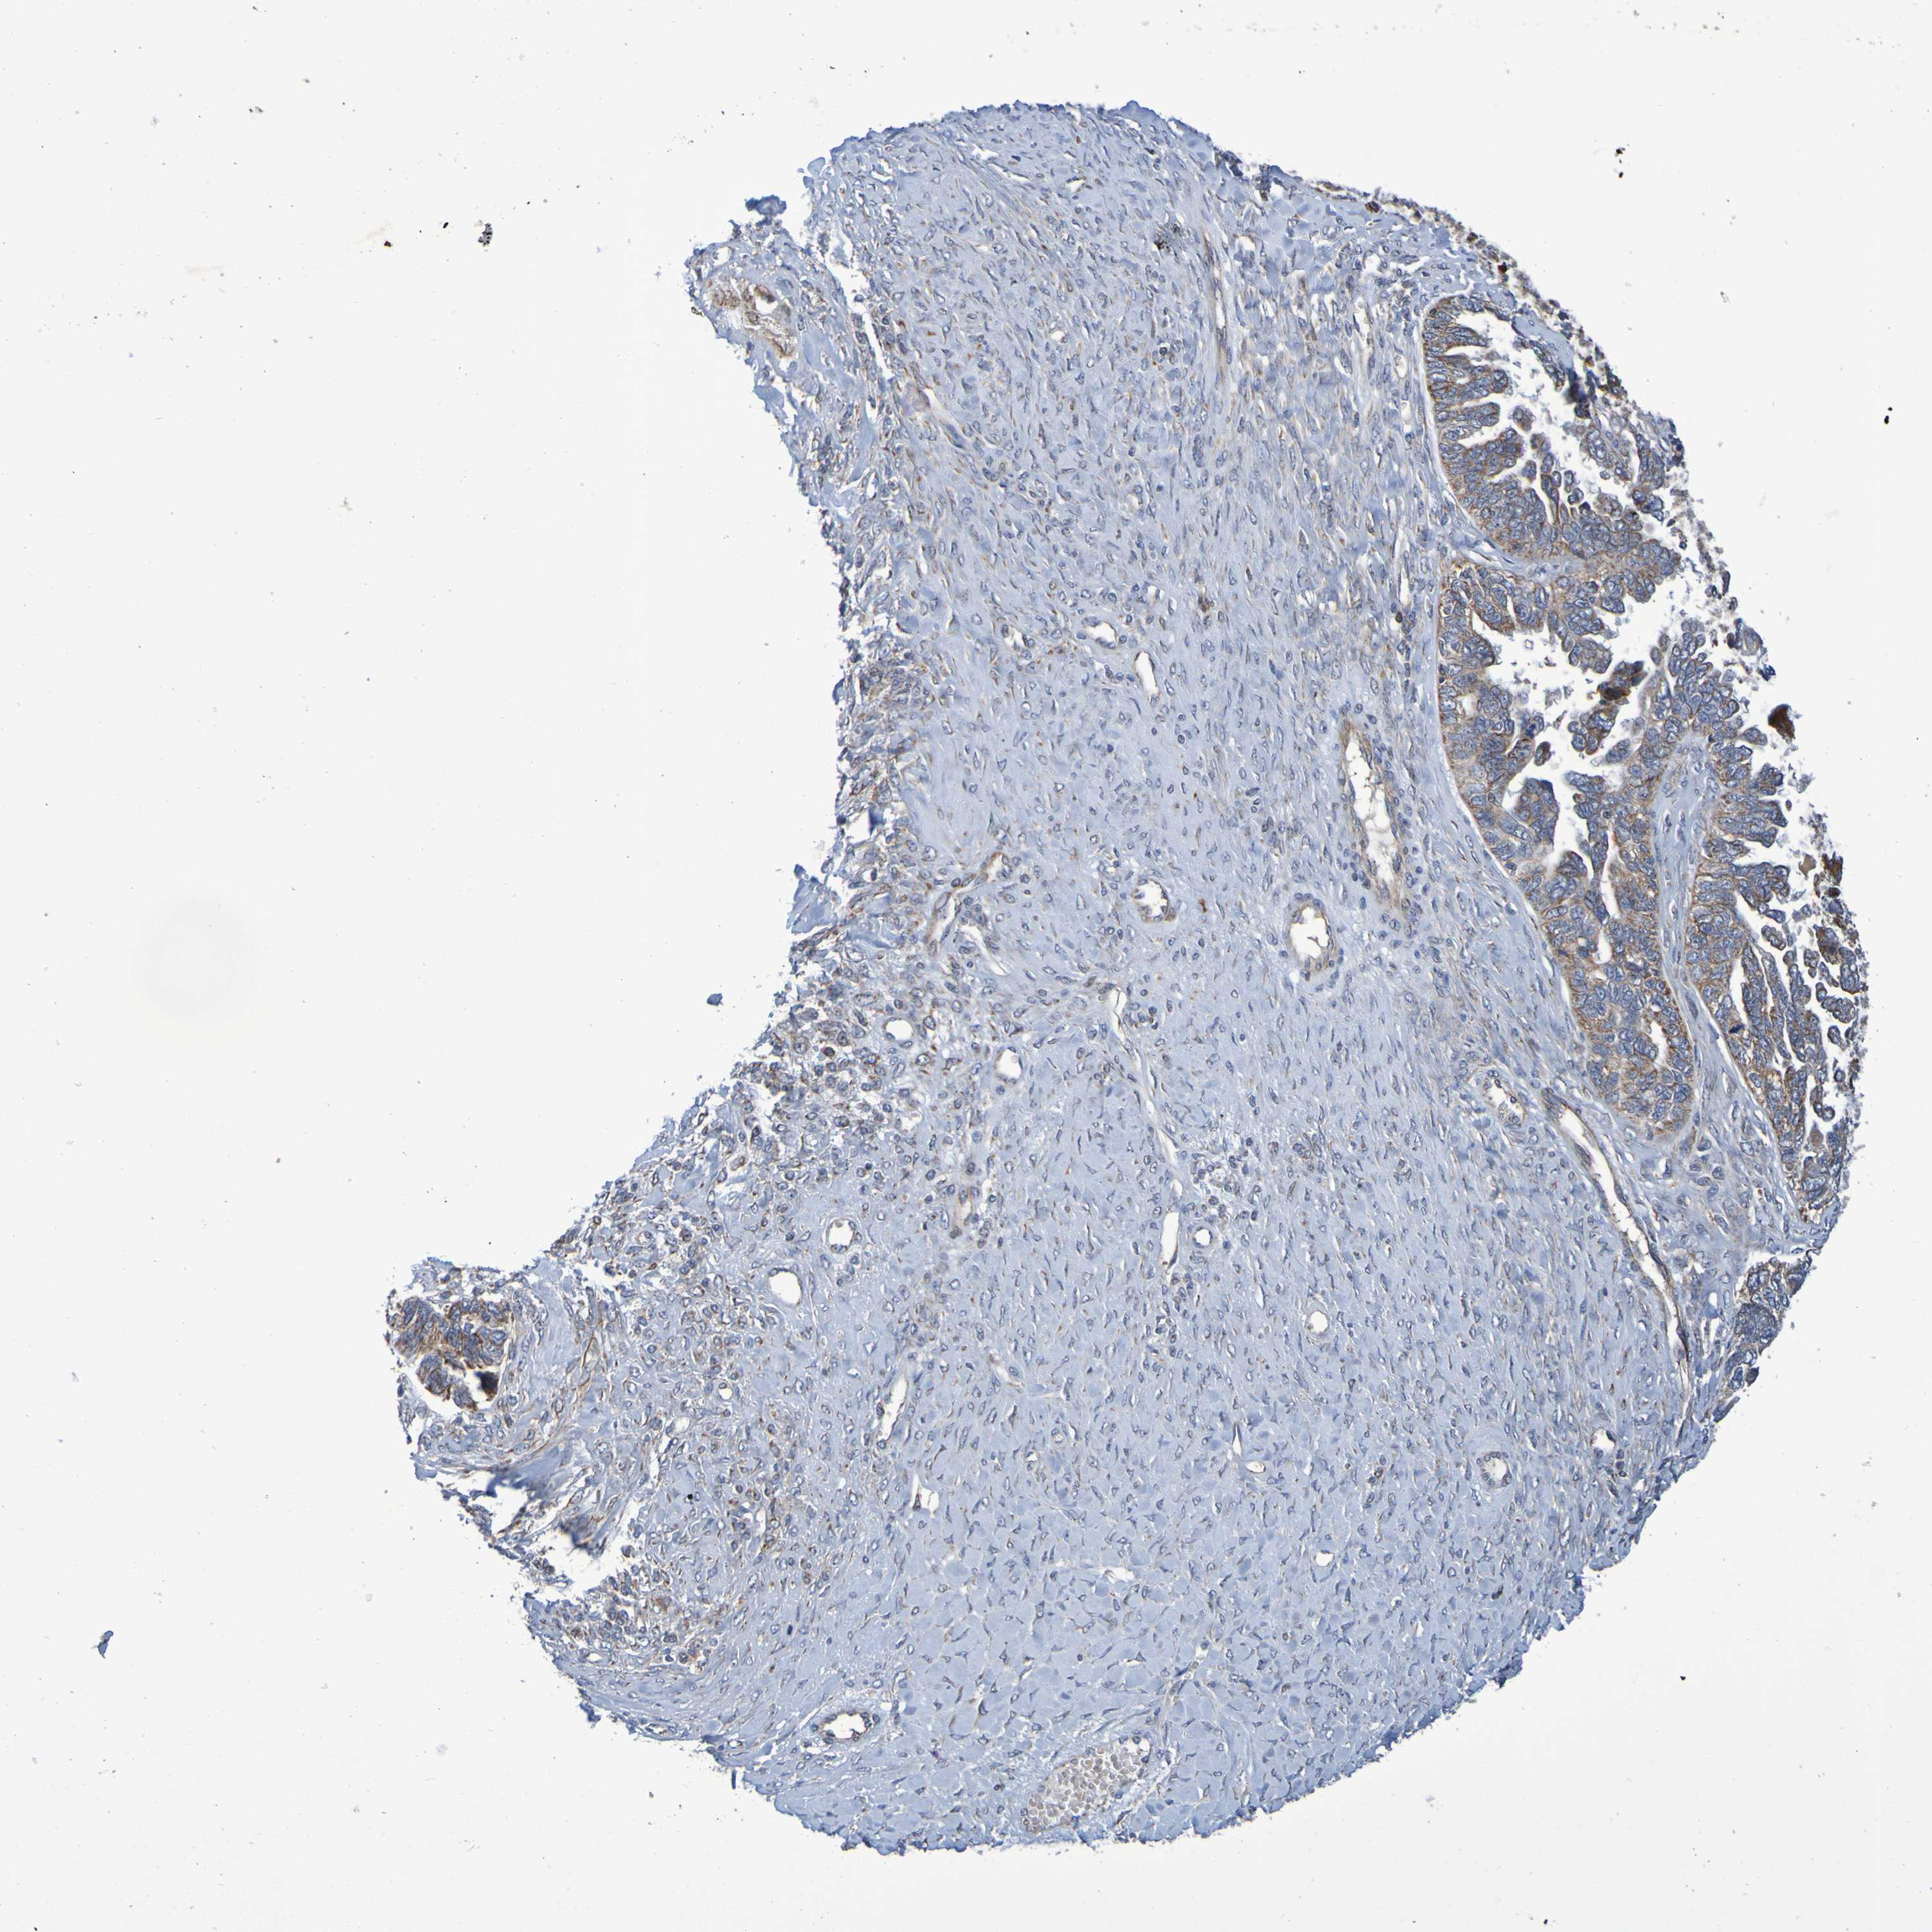

OVARIAN CANCER - Protein expressioni

A mouse-over function shows sample information and annotation data. Click on an image to view it in a full screen mode. Samples can be filtered based on level of antibody staining by selecting one or several of the following categories: high, medium, low and not detected. The assay and annotation is described here.

Note that samples used for immunohistochemistry by the Human Protein Atlas do not correspond to samples in the TCGA dataset.

Antibody stainingi

Antibody staining in the annotated cell types in the current human tissue is reported as not detected, low, medium, or high, based on conventional immunohistochemistry profiling in selected tissues. This score is based on the combination of the staining intensity and fraction of stained cells.

Each image is clickable and will lead to virtual microscopy that enables deeper exploration of all samples and also displays staining intensity scores, fraction scores and subcellular localization as well as patient and tissue information for each sample.

Antibody HPA010980

Antibody HPA011408

Staining

High

Medium

Low

Not detected

Intensity

Strong

Moderate

Weak

Negative

Quantity

>75%

75%-25%

<25%

None

Location

Nuclear

Cytoplasmic/membranous

Cytoplasmic/membranous,nuclear

Cystadenocarcinoma, serous, NOS

Carcinoma, endometroid

Cystadenocarcinoma, mucinous, NOS

Carcinoma, NOS